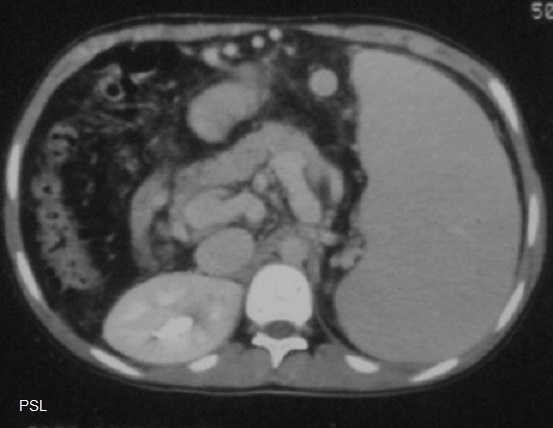

Aspect lesionelle

de micronodulaire diffuse de taille variable de 2-4mm à

hypodense d'une lymphome maligne de la rate . Image

radiologique TDM plus C+ de contrast

phase veineuse , coupe axial |